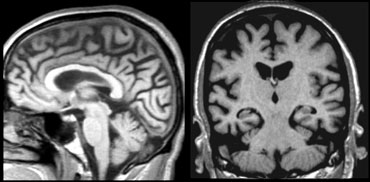

Coronal image of the hippocampus. Coronal image of the hippocampus.

The coronal image shows the hippocampus, the main structure involved in many forms of dementia.

The MTA-score should be rated on coronal T1-weighted images at a consistent slice position.

Select a slice through the corpus of the hippocampus, at the level of the anterior pons.

The score is based on a visual rating of the width of the choroid fissure, the width of the temporal horn, and the height of the hippocampal formation.

• score 0: no atrophy

• score 1: only widening of choroid fissure

• score 2: also widening of temporal horn of lateral ventricle

• score 3: moderate loss of hippocampal volume (decrease in height)

• score 4: severe volume loss of hippocampus

< 75 years: score 2 or more is abnormal.

> 75 years: score 3 or more is abnormal.